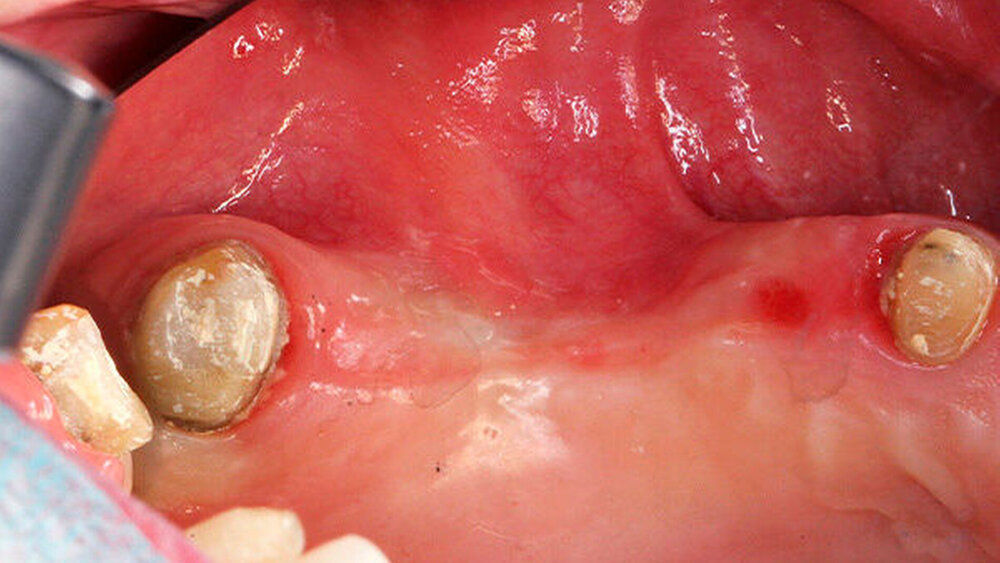

Die Schnittführung wurde nach dem Pillar-Sockel-Design (Blume) vorgenommen. Dabei liegt die Inzision weit im Vestibulum und verbindet zwei vertikale Entlastungsschnitte. Im Gegensatz zu der herkömmlichen krestalen Schnittführung bleibt das Periost über dem augmentierten Bereich damit völlig intakt. Nach der streng subperiostalen Präparation erfolgte die Kontrolle der Passung des CAD/CAM-Blocks. Ein ganz entscheidender Punkt ist, vor jeglichem Kontakt des Blockes mit Blut diesen in steriler Kochsalzlösung und am besten in der PRF-Flüssigkeit zu wässern, sodass sich keine Poren des Blocks mit Blutkoageln verschließen und innerhalb des Blocks ein nicht mit Blut gefüllter Hohlraum bildet. Vor der Befestigung des Blocks wurde die Kompakta des Empfängerbetts mit einer kleinen Kugelfräse mehrfach perforiert um sogenannte Bleeding Points zu setzen, die die Durchblutung des Knochenblocks gewährleisten. Mit zwei Osteosyntheseschrauben mit dem Durchmesser 1,5 mm und der Länge 9 mm wurde der allogene Knochenblock rotationssicher fixiert. Das Augmentat wurde mit einer dünnen Schweinepericard-Membran (Jason membrane, botiss biomaterials GmbH, Vertrieb Straumann) und der PRF-Membran abgedeckt. Der spannungsfreie Wundverschluss erfolgte mit der modifizierten vertikalen Matratzennaht nach Laurrell mit resorbierbarem Nahtmaterial (Vicryl 4.0). Postoperativ wurde ein Oberkiefer-DVT angefertigt. Die Nahtentfernung wurde im Rahmen der Nachsorgeuntersuchung sieben und 14 Tage postoperativ vorgenommen. Nach einer Heilzeit von sechs Monaten erfolgte die Implantation in Lokalanästhesie unter antibiotischer Abschirmung mit 2 g Amoxicillin oral eine Stunde präoperativ. Die Schnittführung erfolgte krestal, und nach subperiostaler Präparation wurde der Knochenblock dargestellt und die Osteosyntheseschrauben wurden entfernt. Danach wurden drei Implantate (Straumann) in den Knochenblock gesetzt und mit 0er-Verschlussschrauben abgedeckt. Die Wundrandadaptation erfolgte mit resorbierbarem Nahtmaterial, das bei der Verlaufskontrolle sieben Tage postoperativ vollständig entfernt wurde. Nach dreimonatiger gedeckter Einheilung wurden die Implantate im Rahmen einer Vestibulumplastik freigelegt. Dafür wurde eine erneute krestale Schnittführung regio 14 bis 17 vorgenommen und ein Splitflap präpariert. Der vestibuläre Wundrand wurde mit Einzelknopfnähten im Vestibulum fixiert. Im Bereich der Implantate wurde der Splitflap perforiert, um die Abdeckschrauben gegen Gingivaformer auszutauschen, und der Bereich des nun freiliegenden Bindegewebes wurde mit einer 3D-vernetzten Kollagenmatrix (mucoderm, botiss biomaterials GmbH, Vertrieb Straumann) abgedeckt. Diese wurde zunächst gewässert, um die Verarbeitung zu erleichtern, und an den Stellen der Gingivaformer gestanzt. Die Nahtentfernung erfolgte neun Tage postoperativ. (Abb. 1a bis 1f).